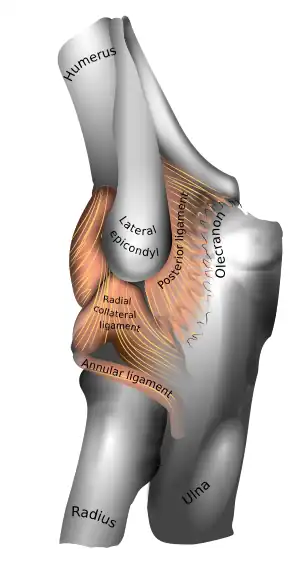

Left elbow-joint

Left: anterior and ulnar collateral ligaments

Right: posterior and radial collateral ligaments

The elbow, like other joints, has ligaments on either side. These are triangular bands which blend with the joint capsule. They are positioned so that they always lie across the transverse joint axis and are, therefore, always relatively tense and impose strict limitations on abduction, adduction, and axial rotation at the elbow.[8]

The ulnar collateral ligament has its apex on the medial epicondyle. Its anterior band stretches from the anterior side of the medial epicondyle to the medial edge of the coronoid process, while the posterior band stretches from posterior side of the medial epicondyle to the medial side of the olecranon. These two bands are separated by a thinner intermediate part and their distal attachments are united by a transverse band below which the synovial membrane protrudes during joint movements. The anterior band is closely associated with the tendon of the superficial flexor muscles of the forearm, even being the origin of flexor digitorum superficialis. The ulnar nerve crosses the intermediate part as it enters the forearm.[8]

The radial collateral ligament is attached to the lateral epicondyle below the common extensor tendon. Less distinct than the ulnar collateral ligament, this ligament blends with the annular ligament of the radius and its margins are attached near the radial notch of the ulna.[8]